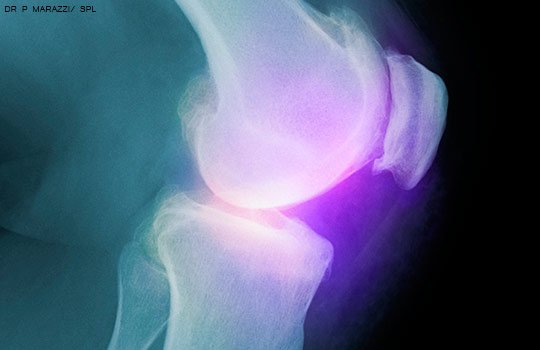

Recomiendan no hacer artroscopía en artrosis de rodilla

17 mayo 2017